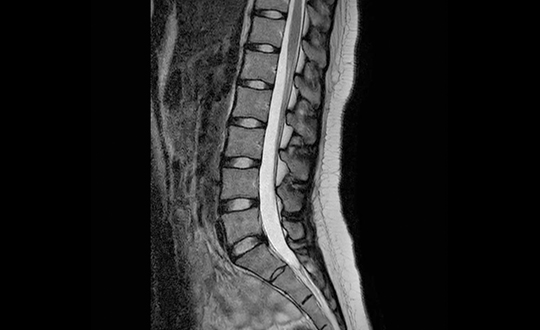

MRI・CT・レントゲンなどの画像検査に迅速かつ確実に対応できるよう、

専門の検査部門を設置。検査依頼は随時受付けており、

PACSによる結果共有により、診療現場でのスムーズな活用が可能です。

院内には高性能な最新機器を導入しており、精度の高い検査をスピーディーに実施。

検査画像も迅速に参照できるため、検査結果の共有がスムーズに行えます。

診療所・クリニックから検査のご依頼、予約をしていただき、 当病院にて画像検査を実施いたします。検査実施後は、 クラウドを通じてスムーズに画像のご共有をいたします。 必要に応じて読影も対応可能です。

DICOM画像・レポートをオンラインで速やかに参照・ダウンロードできます。

しずおか整形外科病院では、MRI、CT、レントゲンの検査予約が可能です。

地域の先生方との連携をより強化すべく、最新の検査機器を導入しました。高精度かつ短時間での撮影を実現し、患者様の負担を軽減しながら、より明瞭な画像診断が可能となります。日常的な整形外科疾患から、より専門的な評価が必要な症例まで、地域の診療に役立つ検査体制を整えています。

1.5テスラ高磁場による高画質と、騒音を約80%低減するComforTone技術を搭載。70cmの広い開口部により圧迫感を軽減し、患者様にやさしいMRI検査を行います。